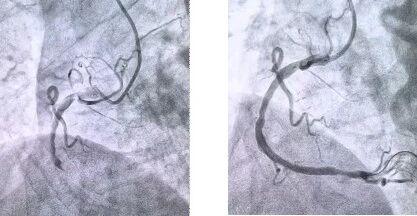

患者抵達(dá)醫(yī)院后,簡化掛號(hào)、繳費(fèi)等中間環(huán)節(jié),迅速溝通病情,需要緊急介入治療,獲得家屬同意,立即送至導(dǎo)管室。造影顯示其右冠狀動(dòng)脈中段完全閉塞,醫(yī)生迅速實(shí)施血栓抽吸,球囊擴(kuò)張和藥物洗脫支架植入術(shù)。36 分鐘后,閉塞血管恢復(fù)正常血流,吳大爺?shù)难獕?、心率逐漸平穩(wěn),胸痛癥狀明顯緩解。術(shù)后三天,他便轉(zhuǎn)入普通病房進(jìn)行康復(fù)訓(xùn)練,重拾健康生活。